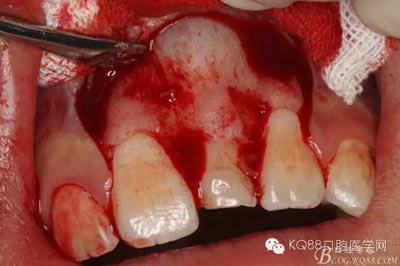

圖9.超聲骨刀去除隆起的骨壁

圖10. 形成梯形骨縫

圖11.掀開(kāi)骨壁。摘除牙瘤及牙囊組織

圖12.摘除囊壁后,暴露出21的切端